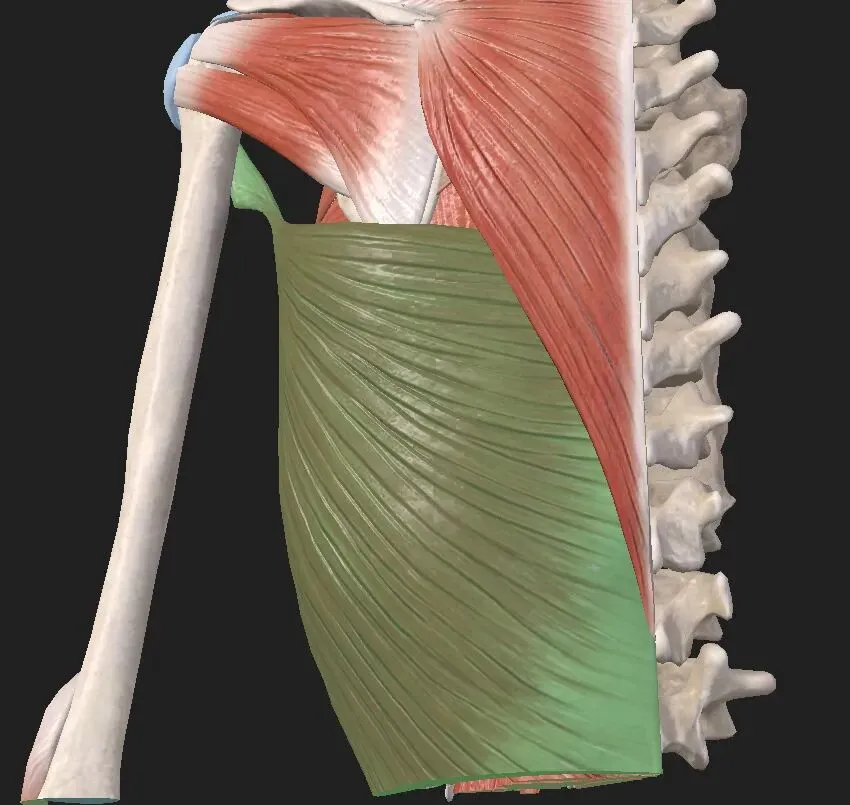

背阔肌

起点:起自第 7~12 胸椎,以及所有腰椎和髋椎棘突上的宽大肌腱(T7~S5)。略略后部,以及下部 3/4 肋面及肩胛下角

止点:止于肱骨结节间沟(肱二头肌沟),正好在肩关节下方。

神经:胸背神经(C6、C7、C8),来自臂丛神经后束

背阔肌有多种功能,从肩关节的角度看,这块肌肉起到外展、内旋和内收肩关节的作用。它是肩关节复合体所有肌肉中唯一一块从脊柱连接到肱骨的肌肉。由于它的下部纤维与下部 3/4 肋相连,故背阔肌也可以通过提肋来协助用力呼吸。

由于背阔肌的斜行纤维交叉并附着于肩胛骨下角,故可通过控制肩胛骨在胸廓周围的侧下方运动来辅助斜方肌下部和前锯肌的活动。该肌肉也是后纵链(外核心系统)的一部分,它连接胸腰筋膜和对侧臀大肌。这些肌肉和筋膜是外核肌筋膜系统的一部分,该系统通过力闭合机制对骶髂关节(SIJ)的稳定性起着不可或缺的作用。

背阔肌也被认为是SIJ、腰椎和胸部的主要稳定器之一,并且能够加速和减缓躯干和脊柱的旋转活动。如果由于对侧(相反)臀大肌存在潜在的减弱或抑制而导致背阔肌过度激活或张力过高而无法发挥作用时,背阔肌将代替臀大肌成为SIJ的稳定结构。这种情况下肩关节生物力学将发生改变,这是由背阔肌与肱骨和肩胛骨特定的附着点的位置决定的。这会导致肩胛骨前倾和下降,造成肩胛提肌和斜方肌上部的过度活动。随着时间的推移,反复出现这些不协调的功能模式将导致患者出现颈部和肩部疼痛。

背阔肌与肩胛骨下角相连,因此它将与菱形肌和肩胛提肌一起帮助肩胛骨完成下降和下回旋。